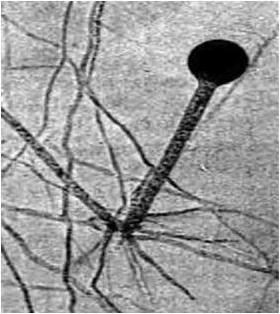

Хламидии существуют в двух формах, различающихся по морфологическим и биологическим свойствам. Инфекционной внеклеточной формой является элементарное тельце (ЭТ), а вегетативной, репродуцирующейся, внутриклеточной – ретикулярное тельце (РТ). Элементарное тельце имеет вид сферы диаметром 0,15 – 0,2 мкм, ретикулярное – имеет структуру типичных грамотрицательных бактерий размером около 1 мкм (рис. 14). В ЭТ содержится больше дисульфидных связей, что позволяет им противостоять осмотическому давлению.

Рис. 14. Цикл размножения хламидий (стадии развития от попадания ЭТ в клетку до выхода ЭТ следующего поколения):

1 – адсорбция элементарного тельца; 2 – проникновение элементарного тельца в клетку; 3 – реорганизация элементарного тельца в ретикулярное тельце; 4 – деление ретикулярного тельца; 5 – созревание ретикулярных телец в элементарные; 6 – накопление ретикулярных телец в эндосоме; 7 – выход хламидий из клетки

Размножение хламидий приводит к формированию включений, известных под названием телец Провачека. В течение 18 – 24 ч развития они локализованы в цитоплазматическом пузырьке, образованном из мембраны клетки-хозяина. Во включении может содержаться от 100 до 500 хламидий. Остановка процесса на этой стадии ведет к персистенции хламидийной инфекции. Далее начинается процесс созревания ретикулярных телец через переходные (промежуточные) тельца в течение 36 – 42 ч развития в ЭТ следующего поколения. Полный цикл репродукции хламидий равен 48 – 72 ч и завершается разрушением пораженной клетки. В случае возникновения для хламидий неблагоприятных метаболических условий этот процесс может затягиваться на более длительный период.

Хламидии могут высвобождаться из инфицированной клетки через узкий ободок цитоплазмы. При этом клетка может сохранять жизнеспособность, этим можно объяснить бессимптомность течения хламидийной инфекции.